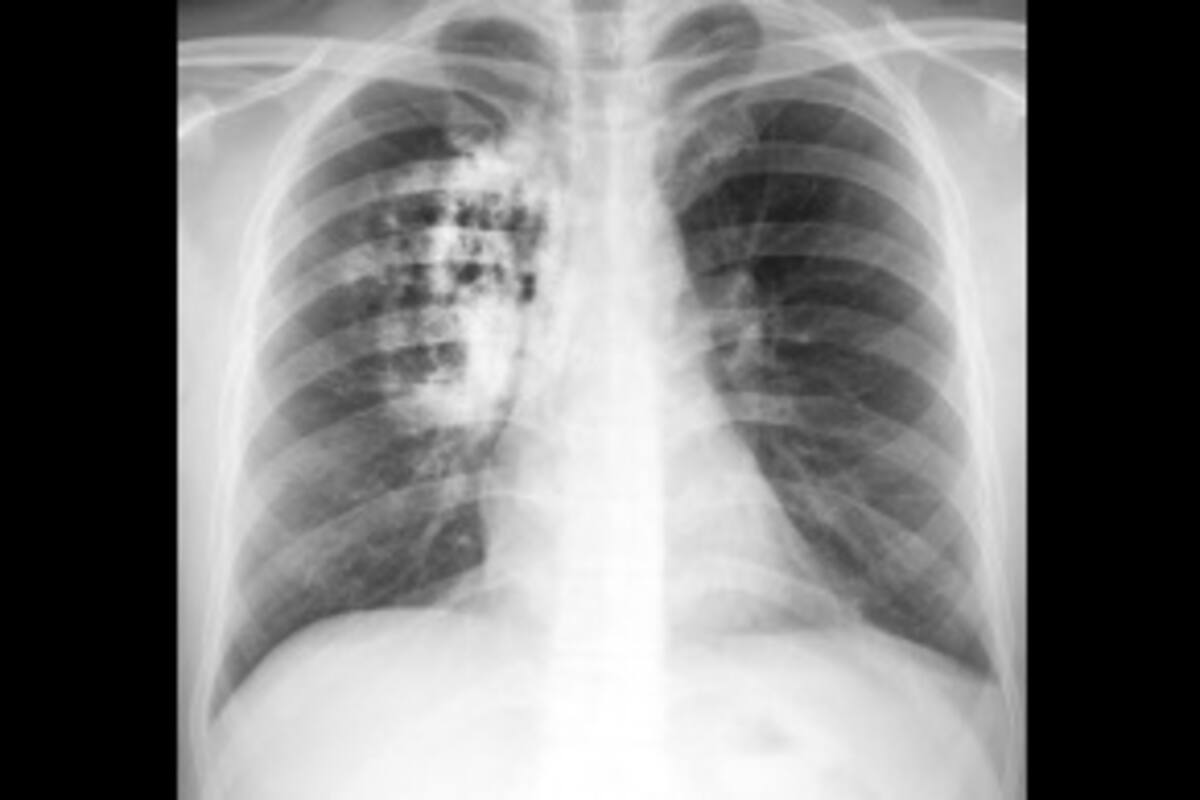

Mata cáncer de pulmón a 222 en un año

Con 222 defunciones registradas en el 2024, el cáncer de pulmón, es el tercer tipo de cáncer que más cobra vidas en Baja California

Mexicali, Baja California.- Con 222 defunciones registradas en el 2024, el cáncer de pulmón, es el tercer tipo de cáncer que más cobra vidas en Baja California, solo después del cáncer de mama y el cáncer de colon.